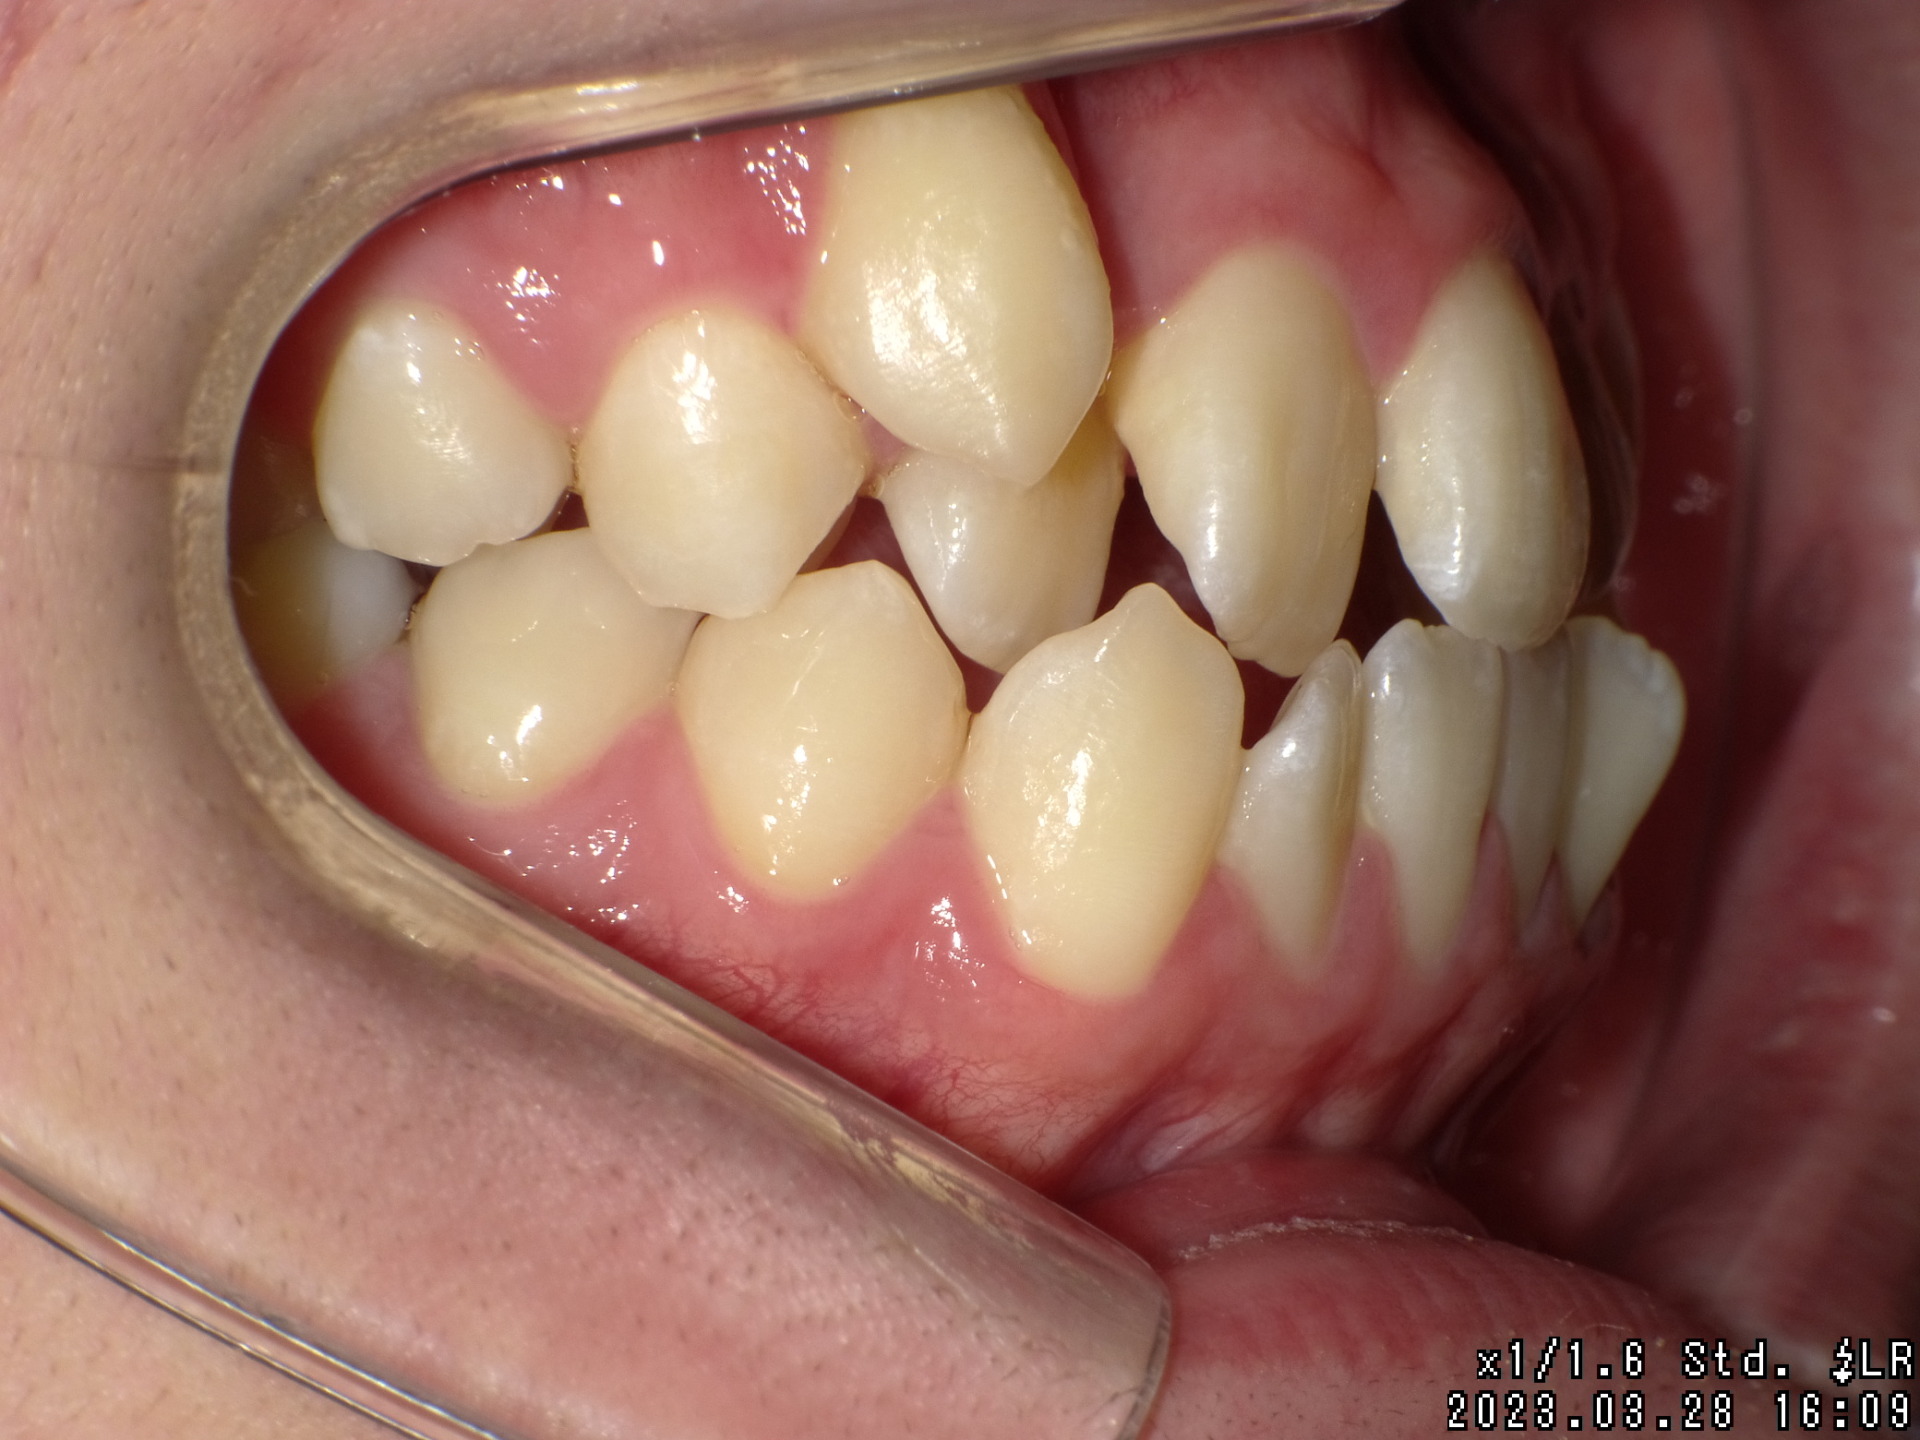

Before

| 症状 | 右上八重歯 上顎正中の著しいずれ |